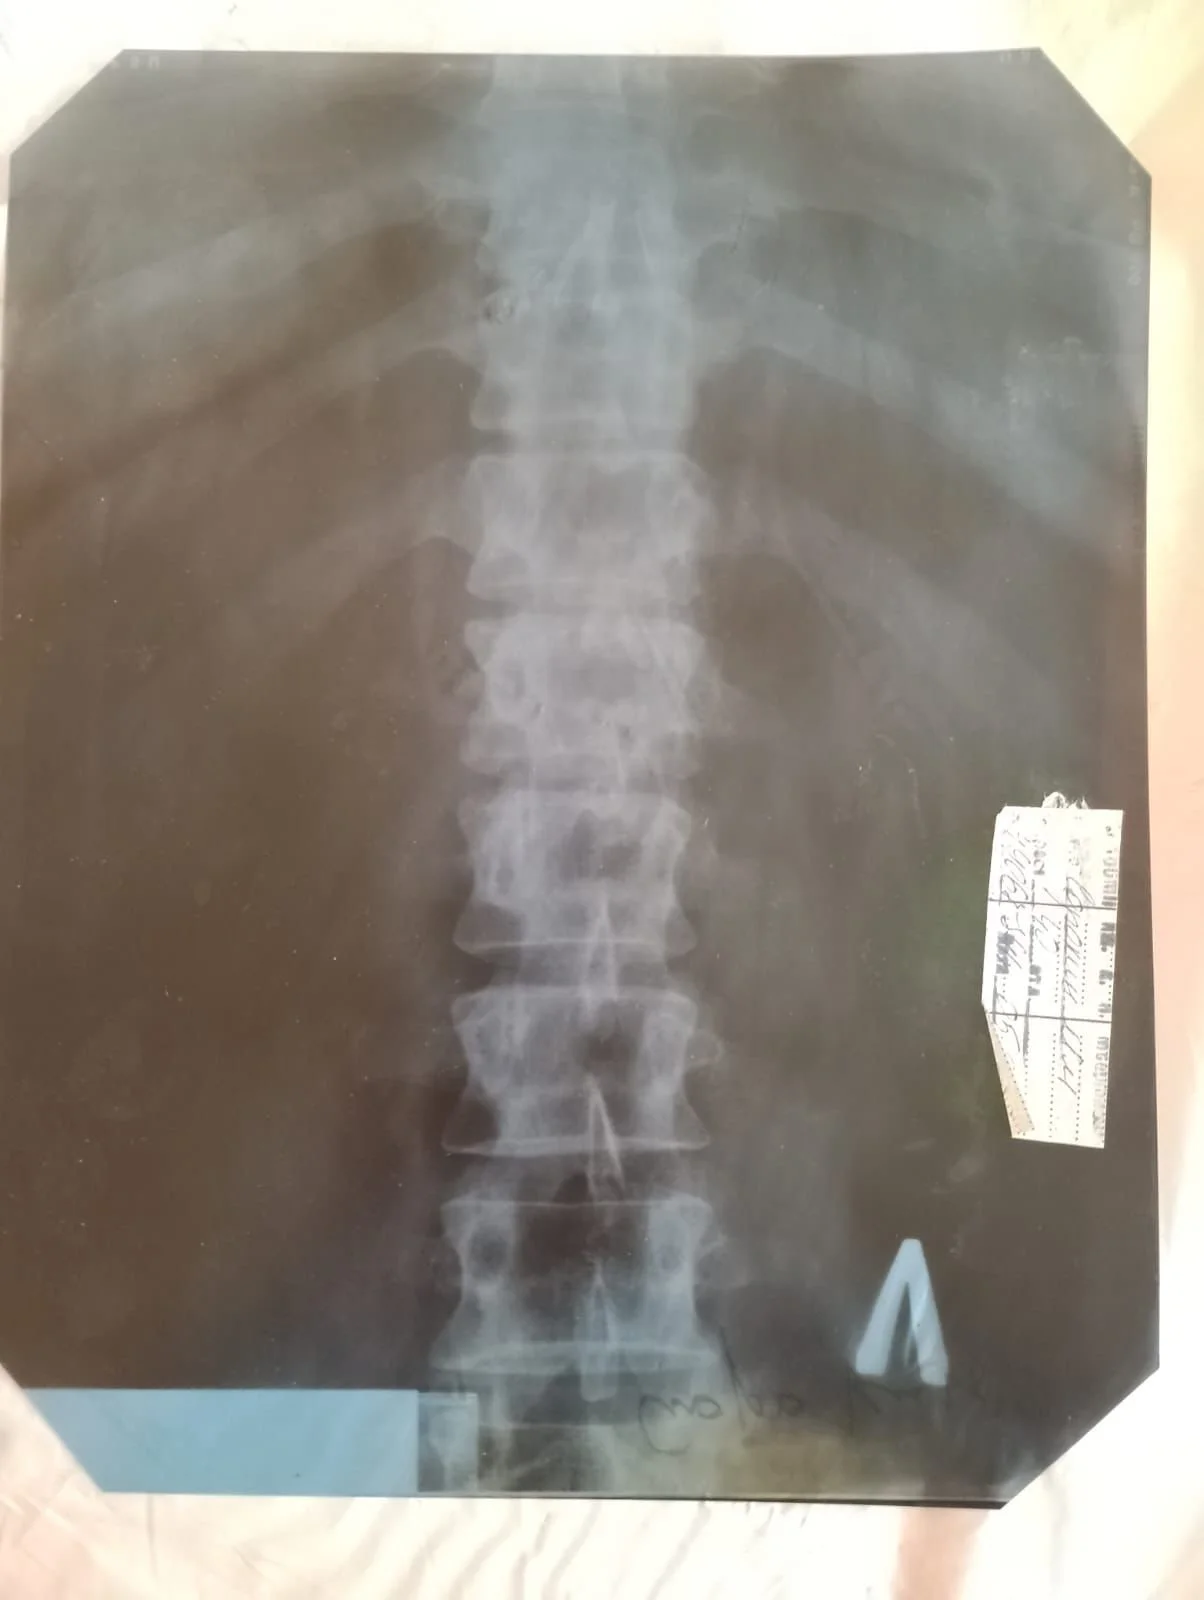

This Ukrainian family lives in Kharkiv, where their home was bombed. In the bombing, Mykhailo suffered a severe back injury, and since then the family has been struggling with the devastation and injustice that has afflicted their country. They have managed to restore a small part of their home with minimal resources, but it remains unsuitable for living in Ukraine’s harsh climate.

They are facing a shortage of water and sanitation services, as their home’s drainage system was destroyed in the attack. However, their greatest hardship is watching Mykhailo, the father and sole provider, suffer from severe pain and immobility. He urgently needs spinal surgery, which must be performed abroad. The nearest and most affordable option is in Poland.